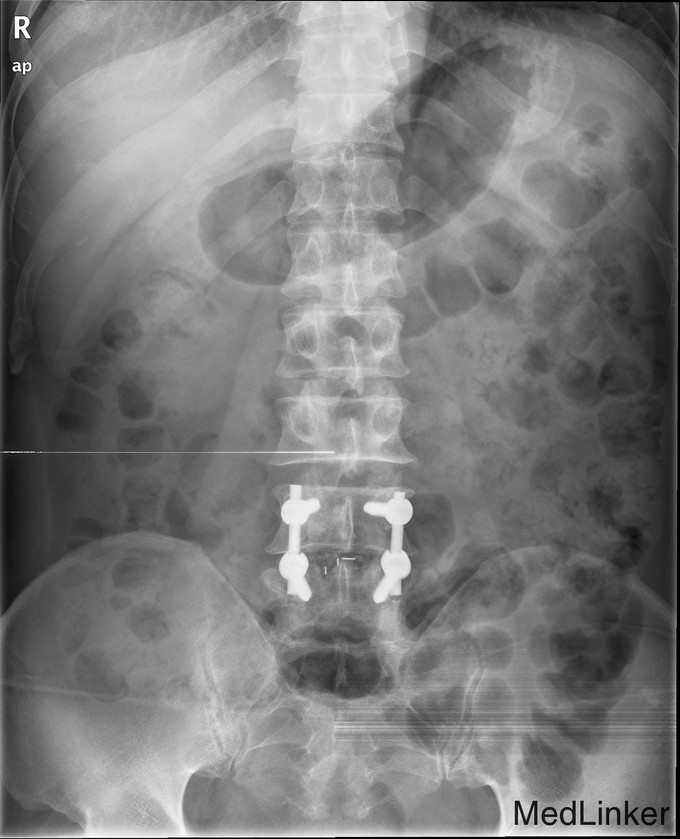

游离型腰椎间盘突出症的手术治疗

腰痛伴右下肢疼痛一周

查体 辅查

腰椎前屈受限,腰34,45右侧棘突旁压痛,放射痛(+),右下肢直腿抬高试验阳性,右小腿皮肤感觉减退

诊断 处理

腰椎间盘突出(游离型) 腰后路减压+髓核摘除椎间融合+植骨内固定